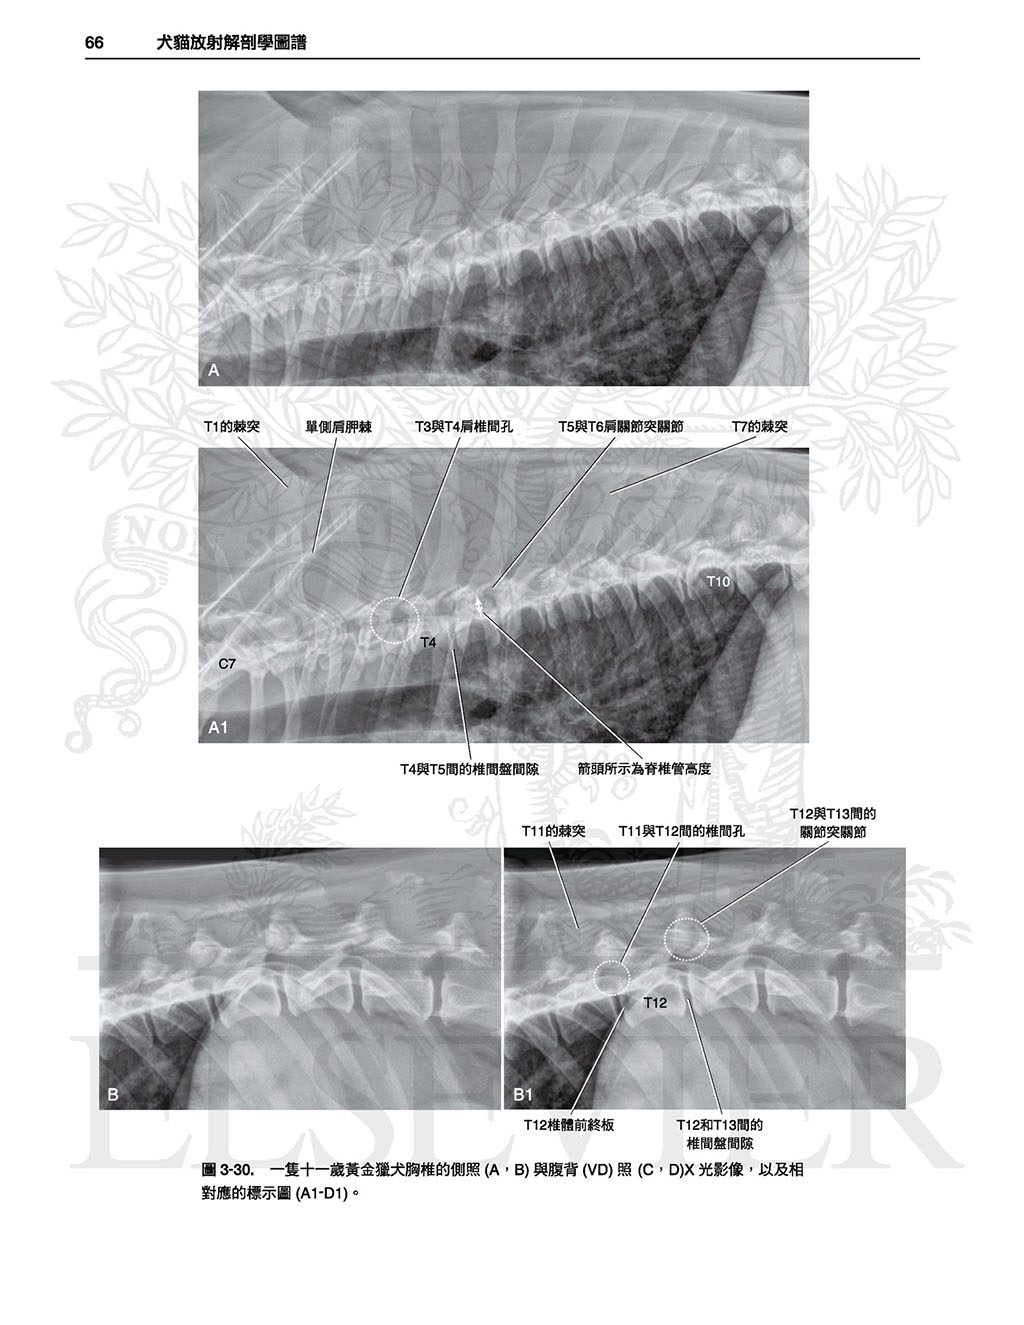

本書並不只是單純的圖譜,各身體部位皆有文字敘述,

因此有助於讀者理解各構造於X光影像學中如此呈現之原因,且提供了讀者對於X光影像學原理基礎性的理解,

有助於對其他正常變異之辨別,雖然可能需要讀者花點心力與圖譜對比使用,但對於判讀能力會有不小的幫助。(本書前言)

以這本詳盡的圖譜學習犬貓正常放射線解剖學的範圍。精通本書將可使診斷更精確並達到更佳的治療效果!

全書皆為高對比的數位影像,除提供正常影像的深入判讀外,亦提供常見且易被誤判為疾病的正常變異;另外並提供多張電腦斷層影像以強調某些結構之影像在放射線學下顯得如此獨特的原因。

本書不但含有豐富圖片,身體各部份皆附上文字描述以協助讀者了解放射解剖學原則,讀者可舉一反三、甚至能以此理解未包含於本書的正常變異。

.詳盡的文字說明及圖片標示

.未標記的原始圖片及標示後的圖片比對

最後,本書並不只是單純的圖譜,各身體部位皆有文字描述,因此有助於讀者 理解各構造於X光影像學中如此呈現之原因,且提供了讀者對於X光影像學原理基礎性的理解,有助於對其他正常變異之辨別,雖然可能需要讀者花點心力與圖譜對比使用,但對於判讀能力會有不小的幫助。

全書皆為高對比的數位影像,除提供正常影像的深入判讀外,亦提供常見且易被誤判為疾病的正常變異;另外並提供多張電腦斷層影像以強調某些結構之影像在放射線學下顯得如此獨特的原因。

本書不但含有豐富圖片,身體各部份皆附上文字描述以協助讀者了解放射解剖學原則,讀者可舉一反三、甚至能以此理解未包含於本書的正常變異。

.詳盡的文字說明及圖片標示

.未標記的原始圖片及標示後的圖片比對

最後,本書並不只是單純的圖譜,各身體部位皆有文字描述,因此有助於讀者 理解各構造於X光影像學中如此呈現之原因,且提供了讀者對於X光影像學原理基礎性的理解,有助於對其他正常變異之辨別,雖然可能需要讀者花點心力與圖譜對比使用,但對於判讀能力會有不小的幫助。